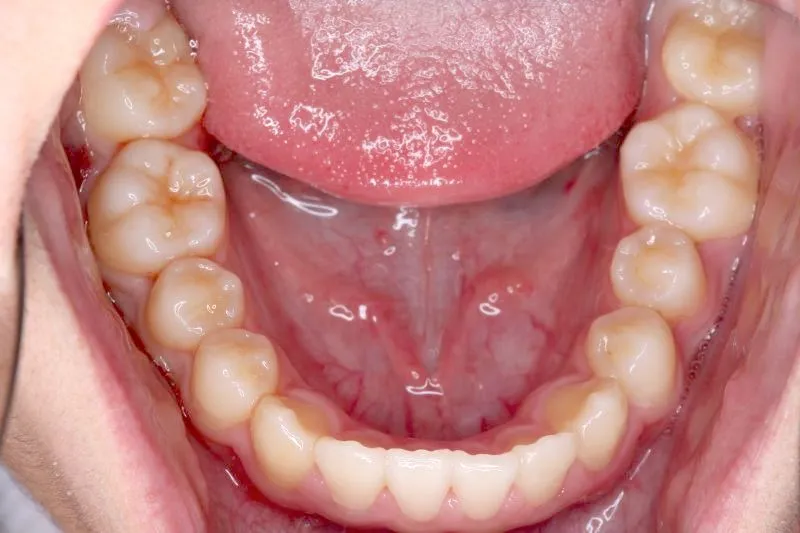

治療終了後

治療回数44回、5年5ヶ月の治療期間で矯正治療を終了しました。

主訴が改善され、ご満足頂きました。